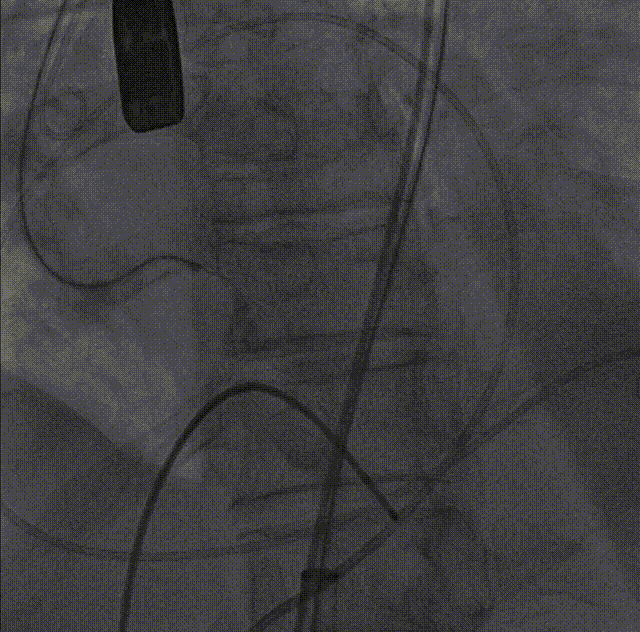

26VenusAplus+snare